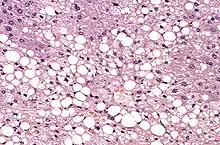

La stéatose est définie comme l'accumulation de matériel lipidique au sein du cytoplasme des hépatocytes[2]. Ces lipides correspondent principalement à des triglycérides[2].

Il existe deux types de stéatose hépatique aux étiologies bien différentes : la stéatose macro-vésiculaire et la stéatose micro-vésiculaire. La stéatose macro-vésiculaire est la plus fréquente majoritairement associée à la consommation excessive d'alcool. Elle est caractérisée par la présence d'une unique vésicule volumineuse au sein du cytoplasme[1],[2]. La stéatose micro-vésiculaire est plus sévère[1] et correspond à la présence de multiples petites vésicules lipidiques[1].

La sévérité de la stéatose est déterminée histologiquement par le pourcentage en hépatocytes comportant une ou des vacuoles dans leur cytoplasme[1]. On parle de stéatose légère en dessous de 30 %, de stéatose modérée entre 30 et 60 % et de stéatose sévère au-delà de 60 %[1]. Cette mesure ne correspond donc pas à un volume en graisse.